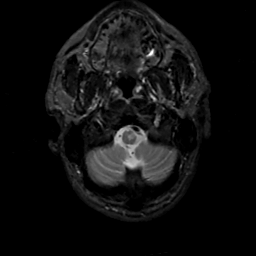

MR Study #14, June 2, 1991 -- Slice #4